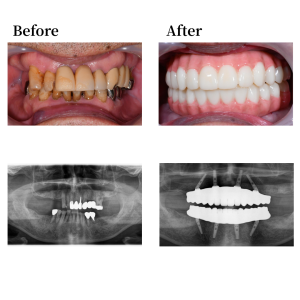

Case 43

背景

患者談。上下の歯のぐらつきや歯の痛みに長年悩まされており、短期間での治療を探していました。友人からオールオン4を紹介され、ネットで検索したところおおたわ歯科医院を知り、相談しようと思いました。福岡県より、当院HPを見て来院されました。短期間で治療が終わる事と、きれいな歯が入ることに魅力を感じ、治療を決意しました。

インプラント詳細

上顎骨の形状を整え、12,22の位置にノーマルインプラントを0度垂直埋入。15, 25 の位置にノーマルインプラントを30度傾斜埋入。下顎も形状を整え、45, 42, 32, 35の位置にそれぞれオールオン4インプラントを埋入。 42, 32の位置に、0度垂直埋入、45, 35の位置に17度傾斜埋入。その後、マルチユニットアバットメントで角度補正を行い、プロビジョナルレストレーション(審美的な仮歯)を装着した。

上部構造詳細

上下顎はUTジルコニアで構成された、フルジルコニアブリッジでファイナルレストレーションとした。焼成されたジルコニアはステインテクニックで着色した。シェードカラーはA2。